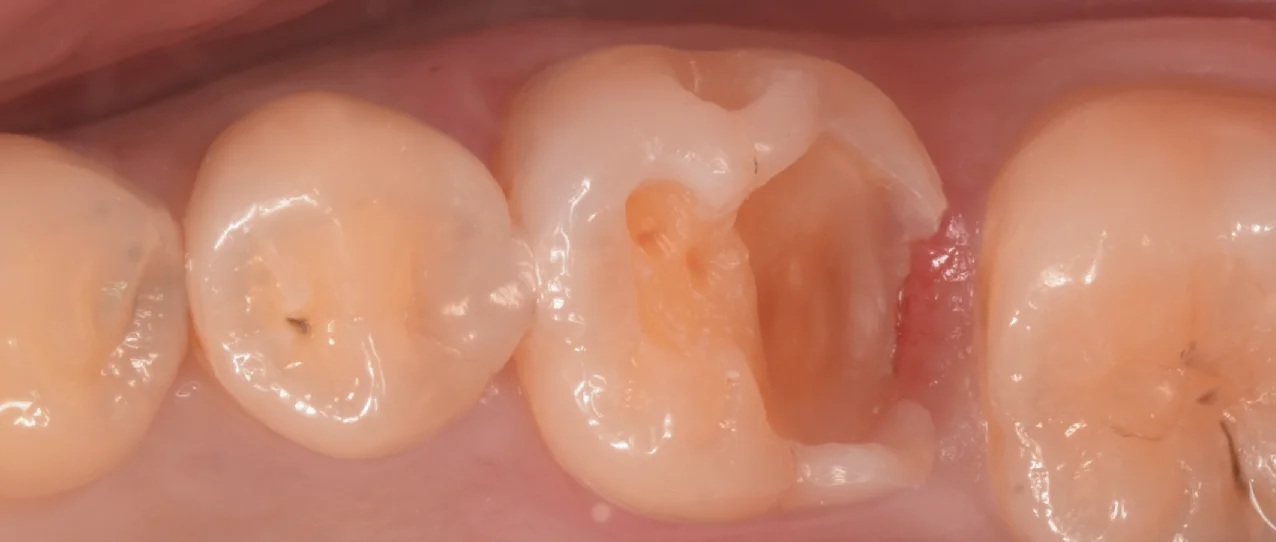

虫歯を取り切ったのがこちらになります。

今回は自費診療ですが、歯茎よりも深すぎる位置まで歯がなくなってしまっていたため、私の技術力でそこに綺麗にラバーダムを行うのが困難と判断し、そのまま他の器具で乾燥状態をしっかりと持続させなら充填していきました。